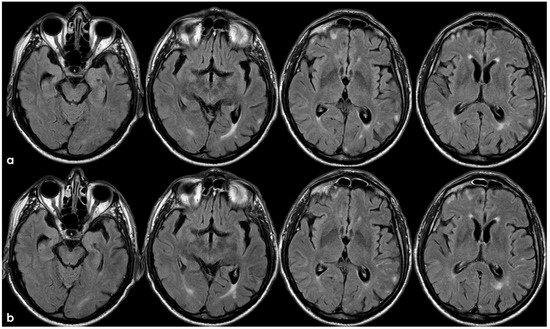

2. December 2013: Sulcal SAH and TFNEs

4. December 2015: Ischemic Stroke